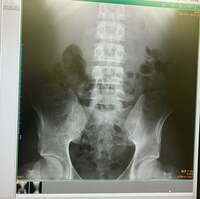

続けて「2023年12月腰痛で違う整形外科へ」と別の病院を受診したことを説明し「レントゲンを撮り、骨に異常ないことを確認し、痛み止めとコルセットを処方されました」と自身のレントゲン写真を公開。その他にも「2023年12月耳から出血で耳鼻科へ」「2024年1月熱と腹痛、吐き気で内科へ」「2024年1月、片側の股関節が痛くなりまた別の整形外科へ」と自身が見舞われた症状を振り返った。